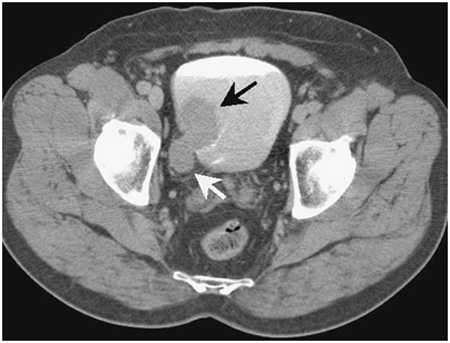

Рисунок. Компьютерная томография.

Рисунок. Изображение, полученное при проведении компьютерной томографии. На нем видно, что опухоль растет не только в просвет мочевого пузыря, но и распространяется на всю глубину стенки мочевого пузыря и за его пределы (стадия Т3).